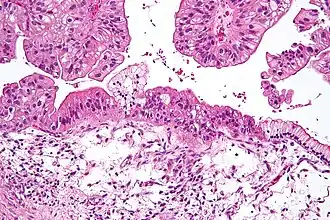

Anatomopathologie

Classification anatomopathologique

Classification histopathologique des carcinomes épithéliaux de l'ovaire (OMS)

- Cystadénocarcinome séreux (42 %)

- Carcinome endométrioïde (15 %)

- Carcinome à cellules claires (6 %), de mauvais pronostic

- Cystadénocarcinome mucineux, rares et de mauvais pronostic[19]

- Carcinome indifférencié

- Tumeur mixte épithéliale